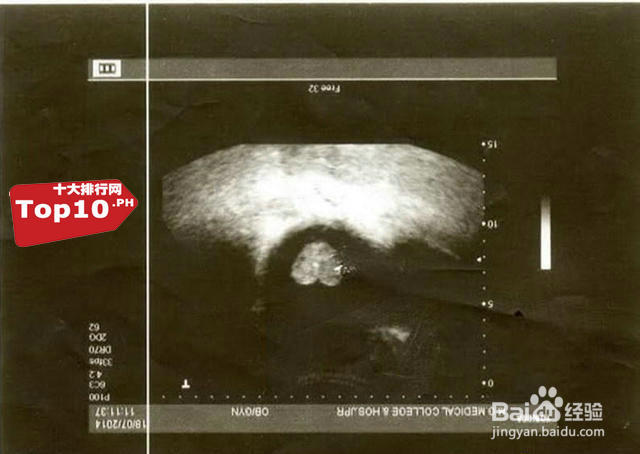

6、5 心形胎盘

胎盘通常是圆形和椭圆形,但有时也会出现一些不规则形状,在一项协作产期项目数据中,不规则外形胎盘被认为新生婴儿体重较低,暗示着不规则形状的胎盘会改变婴儿身体机能。图中是一个心形胎盘。